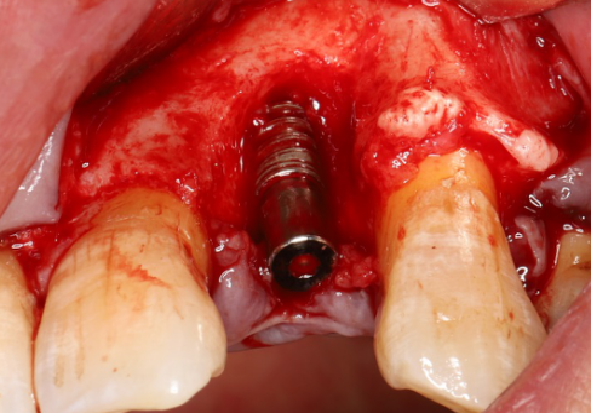

五、标准种植外科备洞程序

使用球钻定位,逐级备孔。

完成备洞。

旋入种植体,初期稳定性为 30N。

直接上愈合基台。